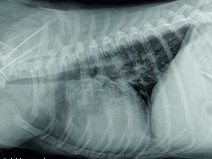

• Soirée La gestation : confirmation, suivi, prédiction de la mise bas et anticipation des risques

Emmanuel Topie (Dipl. ECAR, GERES), fort de son expérience universitaire et libérale, viendra vous présenter les dernières recommandations en matière de reproduction. Il abordera le suivi de la gestation chez la chienne et la chatte, depuis la...